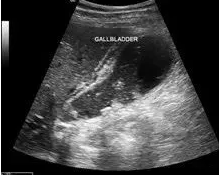

图1,胆囊炎

急性期炎性细胞浸润,组织水肿,超声表现为胆囊增大,胆囊壁增厚,腔内胆汁黏稠,胆囊内透声差,有时可有强回声团,伴声影,也就是伴有胆囊结石,往往嵌顿于胆囊颈管部,胆囊壁可因增厚呈“双边影”改变。

慢性胆囊炎的超声检查表现有胆囊壁增厚、形态缩小或者变形,也可以伴有胆囊结石或(及)胆囊息肉样病变。胆囊炎一般伴有胆囊息肉或者胆结石情况发生。